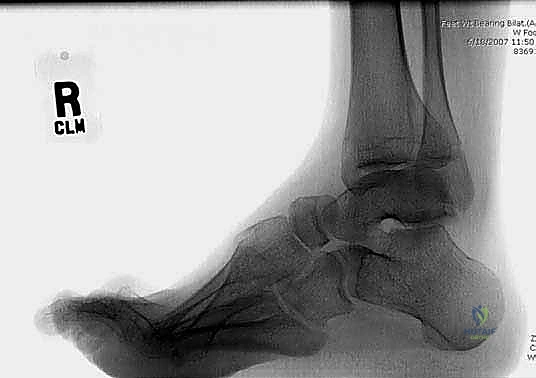

2. التصوير الطبي المتقدم

- الأشعة السينية (X-rays) أثناء الوقوف: لتصوير القدم في وضع تحمل الوزن وقياس الزوايا الهندسية (مثل زاوية Meary وزاوية Hibbs) لتحديد درجة التشوه بدقة.